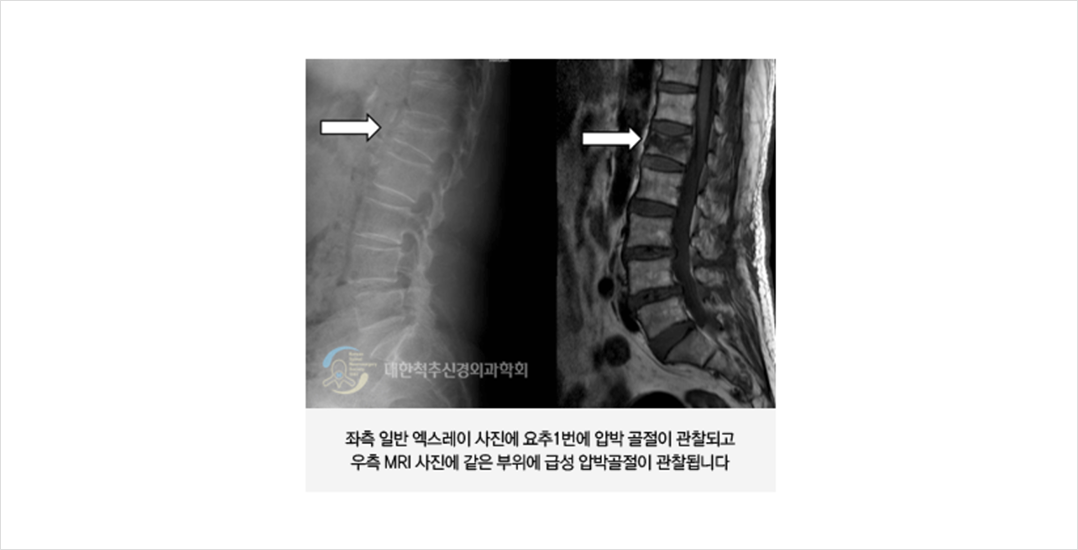

골다공증성 척추 압박골절은 골다공증에 의하여 약화된 척추뼈가 외상에 의하여 압박 변형 되는 것을 의미합니다. 외상의 경우 환자 본인이 기억할 정도인 경우가 많지만, 적지 않은 경우에 환자가 기억하지 못할 정도로 경미한 경우도 있습니다. 이러한 척추 압박 골절은 통증과 척추 변형을 유발하여 노인에게서 장애와 사망 등을 일으키는 원인이 됩니다.

골다공증이 있는 환자에서 외상 후 (일부에서는 다친 것을 기억하지 못하는 경우도 있습니다)에 1-2 주 정도 후에도 국소적인 척추 통증이 지속될 때 의심할 수 있습니다. 대개의 경우 하지로 통증이 내려오지는 않으며 흉곽이나 복부 쪽에 통증이 같이 동반될 수 있습니다.